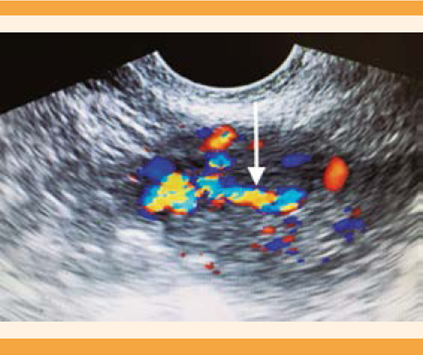

Un par de meses después se reinició la hemorragia uterina anormal, acompañada de dismenorrea incapacitante. El reporte de ultrasonido del mes siguiente reportó: útero en anteversoflexión de bordes regulares, miometrio heterogéneo, eco medio endometrial de 4 mm, en pared anterior y lateralizada a la izquierda una imagen anecoica, alargada, irregular, con grosor de 5 mm, que llegaba al fondo desde donde se proyectaba un trayecto vascular con flujo de alta velocidad hacia el borde distal de la cavidad endometrial (Figura 1). La histeroscopia diagnóstica reportó una lesión de tipo polipoide, pulsátil, irregular, sincrónica a frecuencia cardiaca, de 0.6 x 0.5 mm, localizada en la cara anterior izquierda (Figura 2). La biopsia endometrial se reportó con endometrio asincrónico, compatible con consumo de progestágenos. Se inició el tratamiento secuencial con análogo de GnRH (goserelina), implante subdérmico de 3.6 mg una dosis, más 500 mg cada 8 h de etamsilato. A los 30 días, por falta de respuesta clínica, se aplicó una ampolleta intramuscular de 150 mg de medroxiprogesterona. Como complemento terapéutico, al año de iniciado el tratamiento se efectuó un nuevo legrado hemostático. En las siguientes semanas se corroboró por ultrasonido la sospecha de fístula arteriovenosa en el fondo del útero, y se envió al servicio de Radiología intervencionista, en donde propusieron la histerectomía como tratamiento definitivo.

Figura 1 Ultrasonido Doppler de malformación arteriovenosa de útero. En el fondo uterino se observa un flujo Doppler de alta velocidad que se proyecta a la cavidad endometrial.